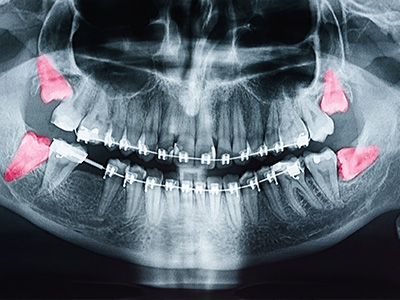

Radiographic imaging is often a key part of the assessment. Panoramic X-rays or cone-beam CT scans provide a detailed view of tooth position, root structure, and relationships to critical anatomy such as the inferior alveolar nerve and the sinus floor. Imaging helps classify the type of impaction and predict surgical complexity, which informs both the treatment recommendation and the discussion about risks and benefits.

Soft tissue impactions often create pockets prone to infection, while bony impactions can place pressure on adjacent tooth roots or be near anatomical structures such as the inferior alveolar nerve. Recognizing the impaction type helps the surgeon predict complexity, discuss potential risks, and plan the most appropriate surgical technique. Proper imaging is essential to make this distinction clearly.

Evaluation begins with a focused medical and dental history and a clinical examination to assess symptoms, mouth opening, and signs of inflammation or trapped food. Imaging is a central component; panoramic radiographs provide an overall view of tooth position while cone-beam CT scans offer detailed three-dimensional information about root anatomy and proximity to nerves and the sinus floor. These findings, combined with age and overall dental needs, guide whether to monitor or recommend extraction.